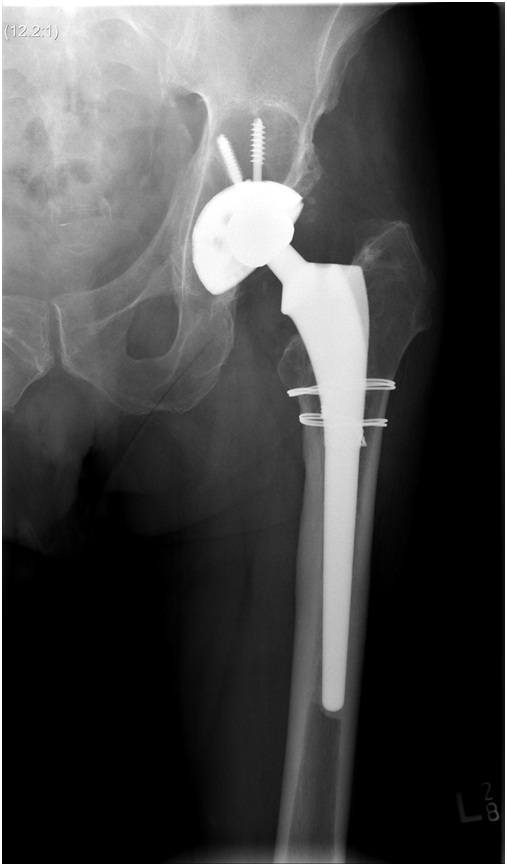

• Loosening or wear - with time a joint replacement may wear out or come loose. Your surgeon can to assess your hip together with an up-to-date Xray to determine if this has occurred

• Problems with the initial operation - occasionally a problem such as fracture or implant malposition will occur in the initial hip operation. This is more likely to happen if the surgeon is inexperienced or does not perform many hip replacements